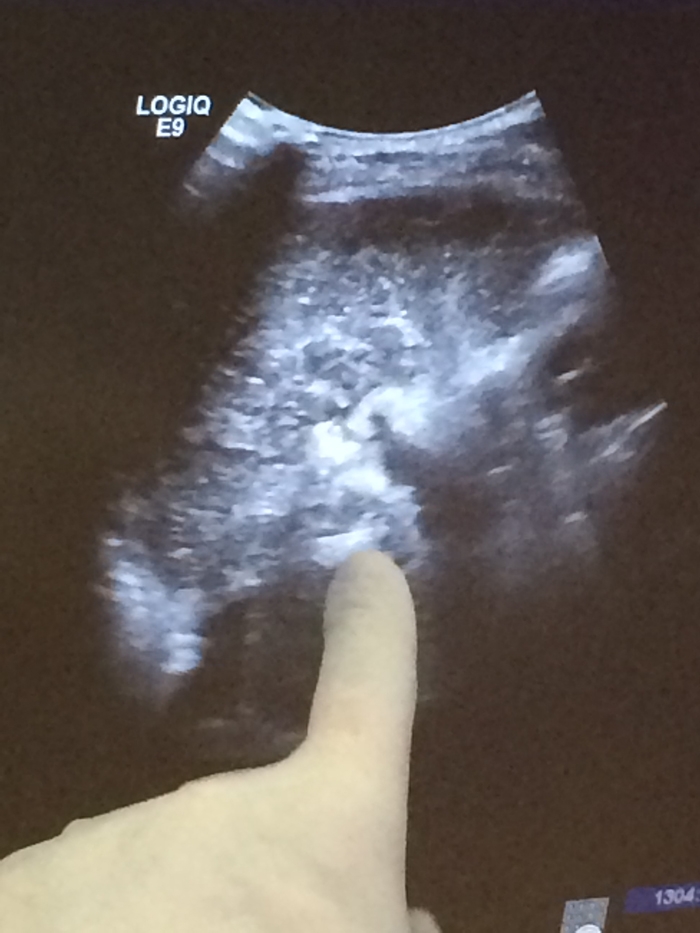

術(shù)中彩超定位尾狀葉腫塊

??? 近日,毛大爺接受了這項治療。在超聲引導(dǎo)下,由皮膚直接插入細(xì)針直達(dá)尾狀葉腫瘤瘤體,通過射頻能量徹底破壞腫瘤。治療過程不到半小時,體表除了一個難辨的針眼外沒有留下任何疤痕。術(shù)后當(dāng)天就下床活動,第三天行動自如。